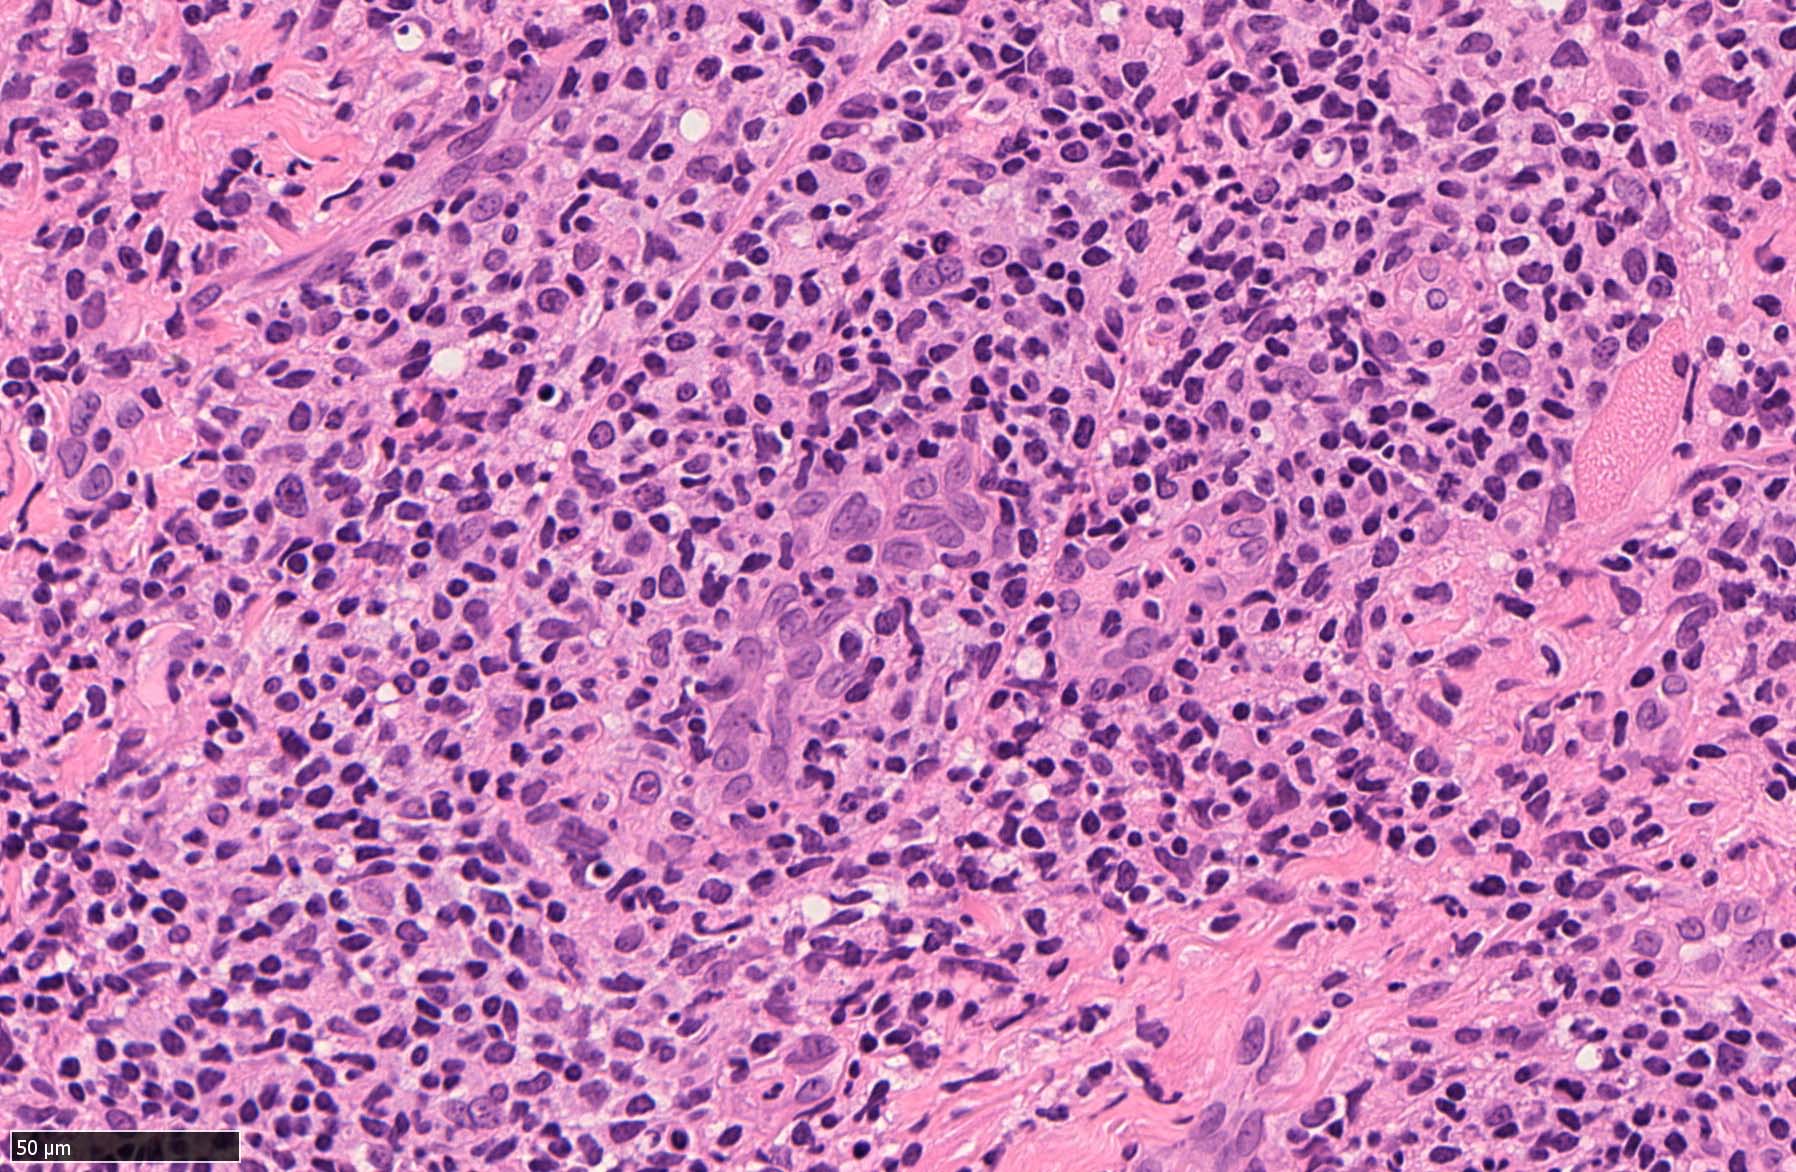

EBV陽性粘膜皮膚潰瘍(EBVMCU)は、EBV陽性の異型大型B細胞および/またはHodgkin/ Reed-Sternberg (HRS)様細胞を含む多形リンパ球浸潤を伴うリンパ増殖性疾患(pleomorphic pattern)で、

典型的には免疫不全/調節障害を有する患者の粘膜および皮膚に発現する。--WHO 5th classificationに記述された定義

定義上はB細胞系のLPDをEBVMCUとしている.